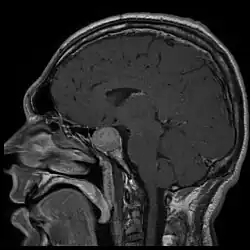

A acromegalia é geralmente causada pela produção excessiva de hormona do crescimento pela hipófise.[1] Em mais de 95% dos casos esta produção excessiva é o resultado de um tumor benigno, como um adenoma de hipófise.[1] A doença não é hereditária.[1] Em casos raros, a acromegalia pode ser causada por um tumor noutra parte do corpo.[1] O diagnóstico consiste em medir os níveis de hormona do crescimento após a ingestão de uma solução de glicose, ou em medir a concentração no sangue do fator de crescimento semelhante à insulina tipo 1.[1] Após o diagnóstico são realizados exames imagiológicos à hipófise para determinar a presença ou não de um adenoma.[1] Quando a produção excessiva de hormona do crescimento ocorre durante a infância, o resultado é uma doença denominada gigantismo, e não acromegalia.[1]